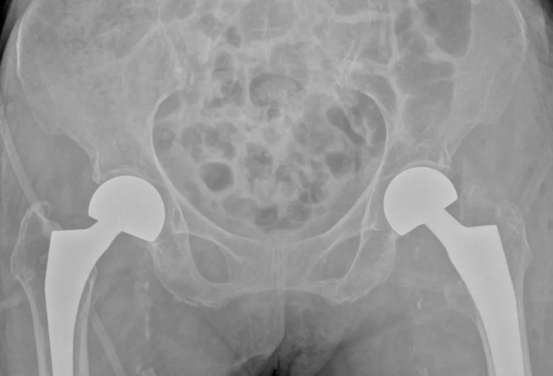

术后床旁X线检查